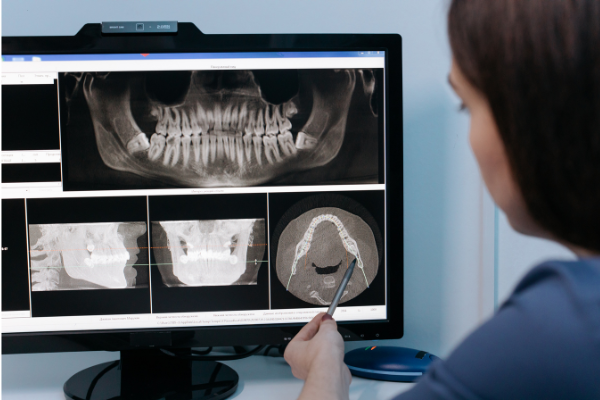

- Your 3D images load on our screen almost right away. We review them with you before you leave.

But here’s what really matters. You get to see it too. We turn the monitor toward you and walk through exactly what we’re looking at. No confusing gray blobs on a tiny film. Real anatomy you can actually understand. Patients tell us that moment changes everything for them, suddenly the treatment plan makes sense.

Same-visit imaging also changes how we plan your care. Say you come in for an oral exam and cleaning, and we notice bone loss around a back molar. Instead of guessing or sending you somewhere else, we capture a 3D scan right then. Within minutes we can see the bone density, the root shape, nearby nerve paths. If you need a dental implant or root canal therapy down the road, we’re already looking at the full picture.

But speed isn’t the only win. Keeping everything under one roof means your scan, your diagnosis, and your treatment plan all come from the same team. Nothing gets lost in a fax. No one misreads a report from a facility that’s never met you. It’s your dentist, your images, your conversation, all happening in real time at our N Tracy Blvd location.